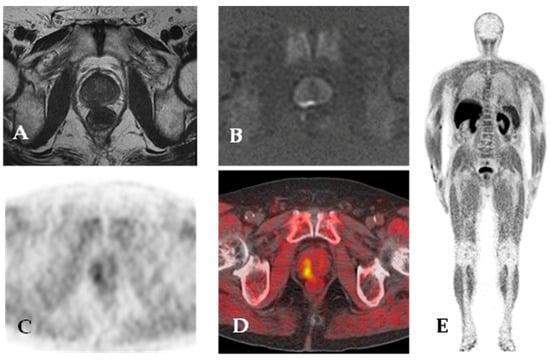

4.3. Prostate-Specific Membrane Antigen

- Ferraro, D.A.; Becker, A.S.; Kranzbühler, B.; Mebert, I.; Baltensperger, A.; Zeimpekis, K.G.; Grünig, H.; Messerli, M.; Rupp, N.J.; Rueschoff, J.H.; et al. Diagnostic Performance of 68Ga-PSMA-11 PET/MRI-Guided Biopsy in Patients with Suspected Prostate Cancer: A Prospective Single-Center Study. Eur. J. Nucl. Med. Mol. Imaging 2021, 48, 3315–3324. [Google Scholar] [CrossRef]

- Bauckneht, M.; Bertagna, F.; Donegani, M.I.; Durmo, R.; Miceli, A.; De Biasi, V.; Laudicella, R.; Fornarini, G.; Berruti, A.; Baldari, S.; et al. The Prognostic Power of 18F-FDG PET/CT Extends to Estimating Systemic Treatment Response Duration in Metastatic Castration-Resistant Prostate Cancer (MCRPC) Patients. Prostate Cancer Prostatic. Dis. 2021, 24, 1198–1207. [Google Scholar] [CrossRef] [PubMed]

- Chen, R.; Wang, Y.; Zhu, Y.; Shi, Y.; Xu, L.; Huang, G.; Liu, J. The Added Value of 18F-FDG PET/CT Compared with 68Ga-PSMA PET/CT in Patients with Castration-Resistant Prostate Cancer. J. Nucl. Med. 2022, 63, 69–75. [Google Scholar] [CrossRef]

- Thang, S.P.; Violet, J.; Sandhu, S.; Iravani, A.; Akhurst, T.; Kong, G.; Ravi Kumar, A.; Murphy, D.G.; Williams, S.G.; Hicks, R.J.; et al. Poor Outcomes for Patients with Metastatic Castration-Resistant Prostate Cancer with Low Prostate-Specific Membrane Antigen (PSMA) Expression Deemed Ineligible for 177Lu-Labelled PSMA Radioligand Therapy. Eur. Urol. Oncol. 2019, 2, 670–676. [Google Scholar] [CrossRef]

- Kepenek, F.; Can, C.; Kömek, H.; Kaplan, İ.; Gündoğan, C.; Ebinç, S.; Güzel, Y.; Agüloglu, N.; Karaoglan, H.; Taşdemir, B. Combination of [68Ga]Ga-PSMA PET/CT and [18F]FDG PET/CT in Demonstrating Dedifferentiation in Castration-Resistant Prostate Cancer. Médecine Nucléaire 2023, 47, 193–199. [Google Scholar] [CrossRef]